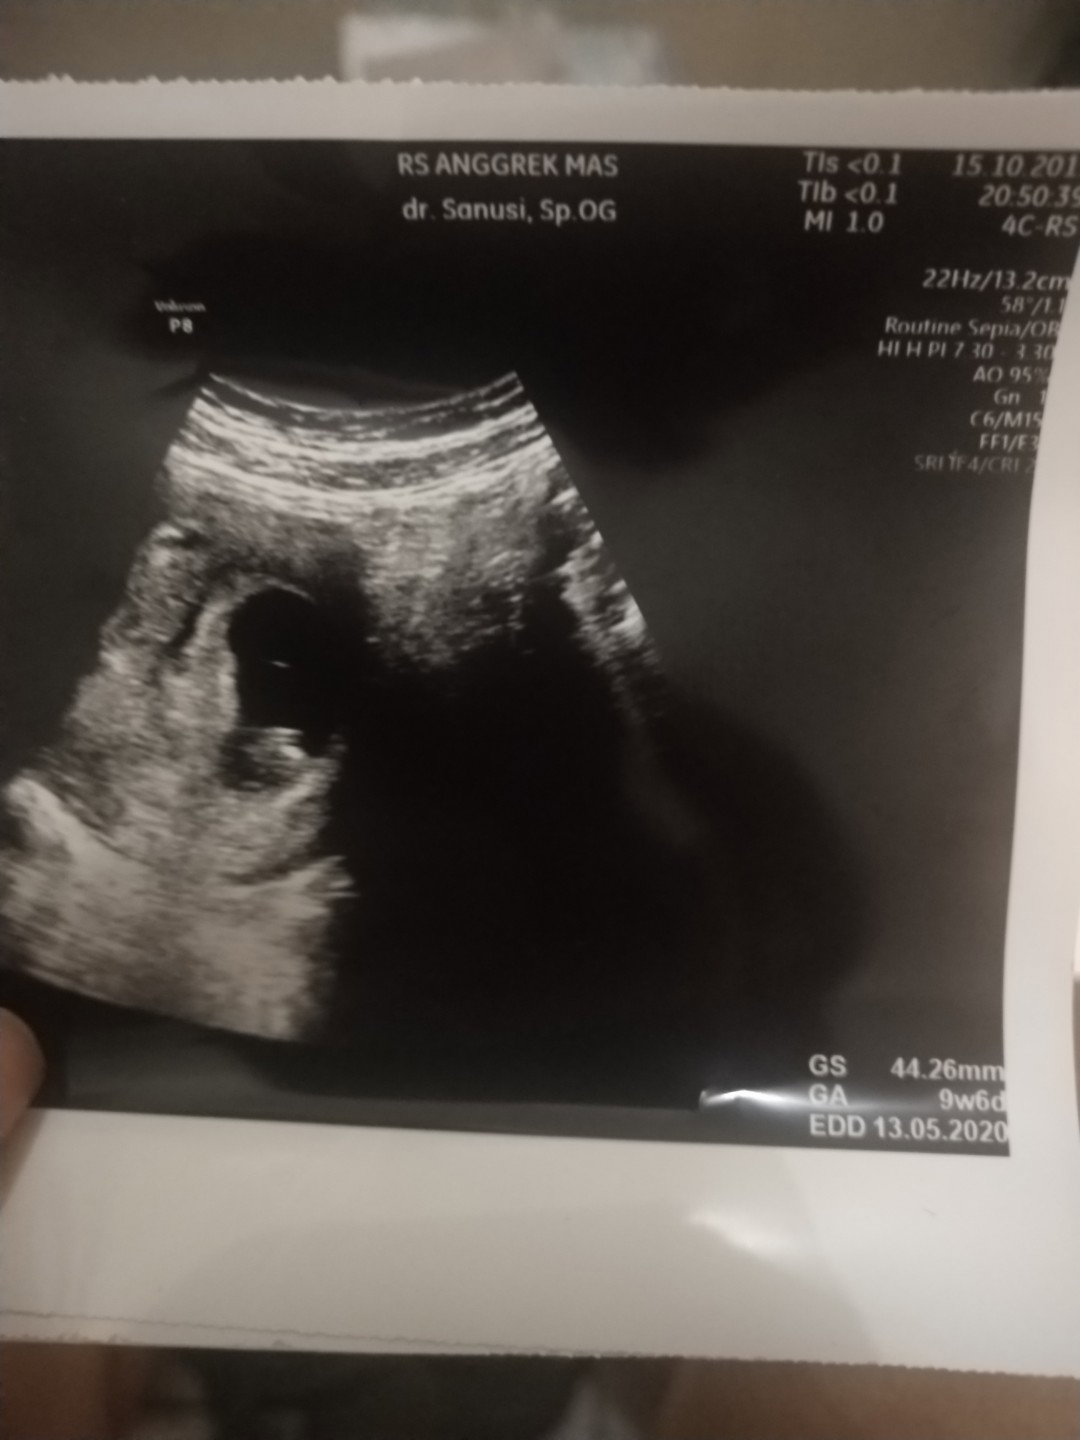

mom mau nanya, hal yang wajar atau tidak diusia 9w6d detak jantung janin belum terdengar ? Ini kehamilan pertama saya , dan saya sangat cemas karna hasil usg kemarin detak jantung janin belum terdengar. Mohon infonya ya mom